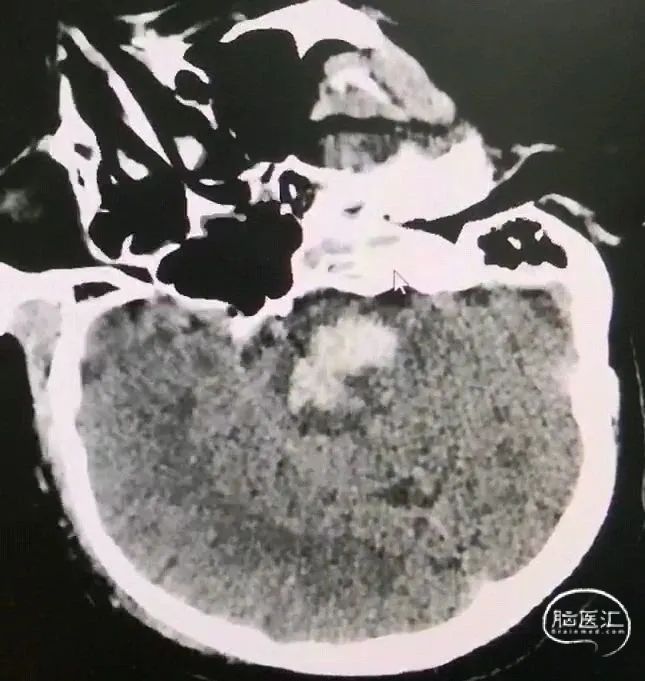

对波及大脑脚、中脑、桥脑上部的上下狭长型血肿,采用经额入路,避开侧脑室,经额叶-内囊前内侧-大脑脚入路,最好沿血肿长轴,靶点选择位置较低、血肿较大的层面;

CT扫描后测算脑干血肿穿刺靶点及路径

脑干血肿引流管经大脑脚入中脑

引流管穿经中脑血肿

引流管准确到达靶点

术后尿激酶应用,术后3天复查CT,血肿引流满意